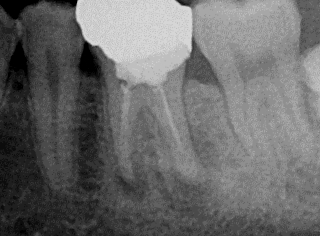

先日、いつもの3ヶ月毎の定期検診にお越しいただき、全体のチェックと共に根管治療部位のレントゲン写真も撮らせていただきました。

この10年症状も無く、もちろん新たなむし歯を作ることなく経過良好で過ごしていただいております。